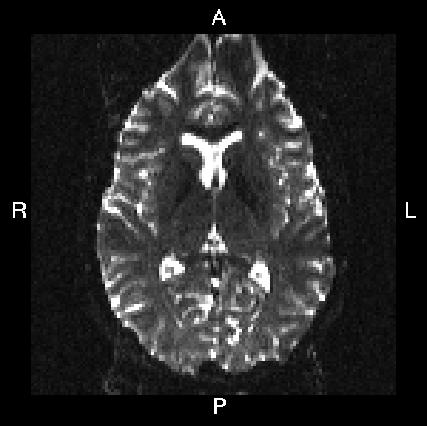

Below you see four examples of images acquired with different phase encoding. Below the images you see what you would find in the PDF protocol generated on a Siemens scanner for these acquisitions. Unfortunately I don't have enough experience of other scanner manufacturers to know where to find the information from those.

If you are uncertain about how to create your own --acqp file I suggest you get your scanner protocol, load your images into FSLVIEW and then find which of the images below that looks most like then one you have. When you have done that compare the "Phase enc." entry below that image with that in your protocol. When you are happy that you have found the right column you can use the three first values from the vector below the image.

| What you see in FSLeyes |

|---|---|---|---|---|

| In Siemens protocol | Phase enc. dir P >> A Echo spacing 0.75 ms EPI factor 128 |

| In --acqp file | 0 1 0 0.095 | 0 -1 0 0.095 | 1 0 0 0.122 | -1 0 0 0.122 |